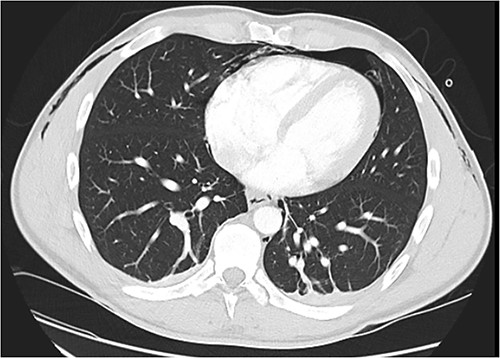

Following extubation, bilateral chest wall subcutaneous emphysema was noted extending to the neck. He also complained of central chest discomfort, without respiratory distress, oxygen desaturation or airway obstruction. Chest X-ray (CXR) revealed pneumomediastinum and surgical emphysema in the lateral chest walls bilaterally. Computed tomography (CT) of the chest, abdomen and pelvis demonstrated large volume subcutaneous emphysema bilaterally in the scrotum, abdominal and chest walls extending to the neck (see Figs 2–5). Gas was noted between the abdominal muscle layers, extraperitoneal and retroperitoneal spaces without pneumoperitoneum (see Figs 5–6). Moderate pneumomediastinum was prominent within the superior and antero-inferior mediastinum without evidence of tracheal or oesophageal injury and an associated small left pneumothorax was noted (see Figs 1–3).

CT chest coronal, pneumomediastinum and bilateral subcutaneous emphysema.